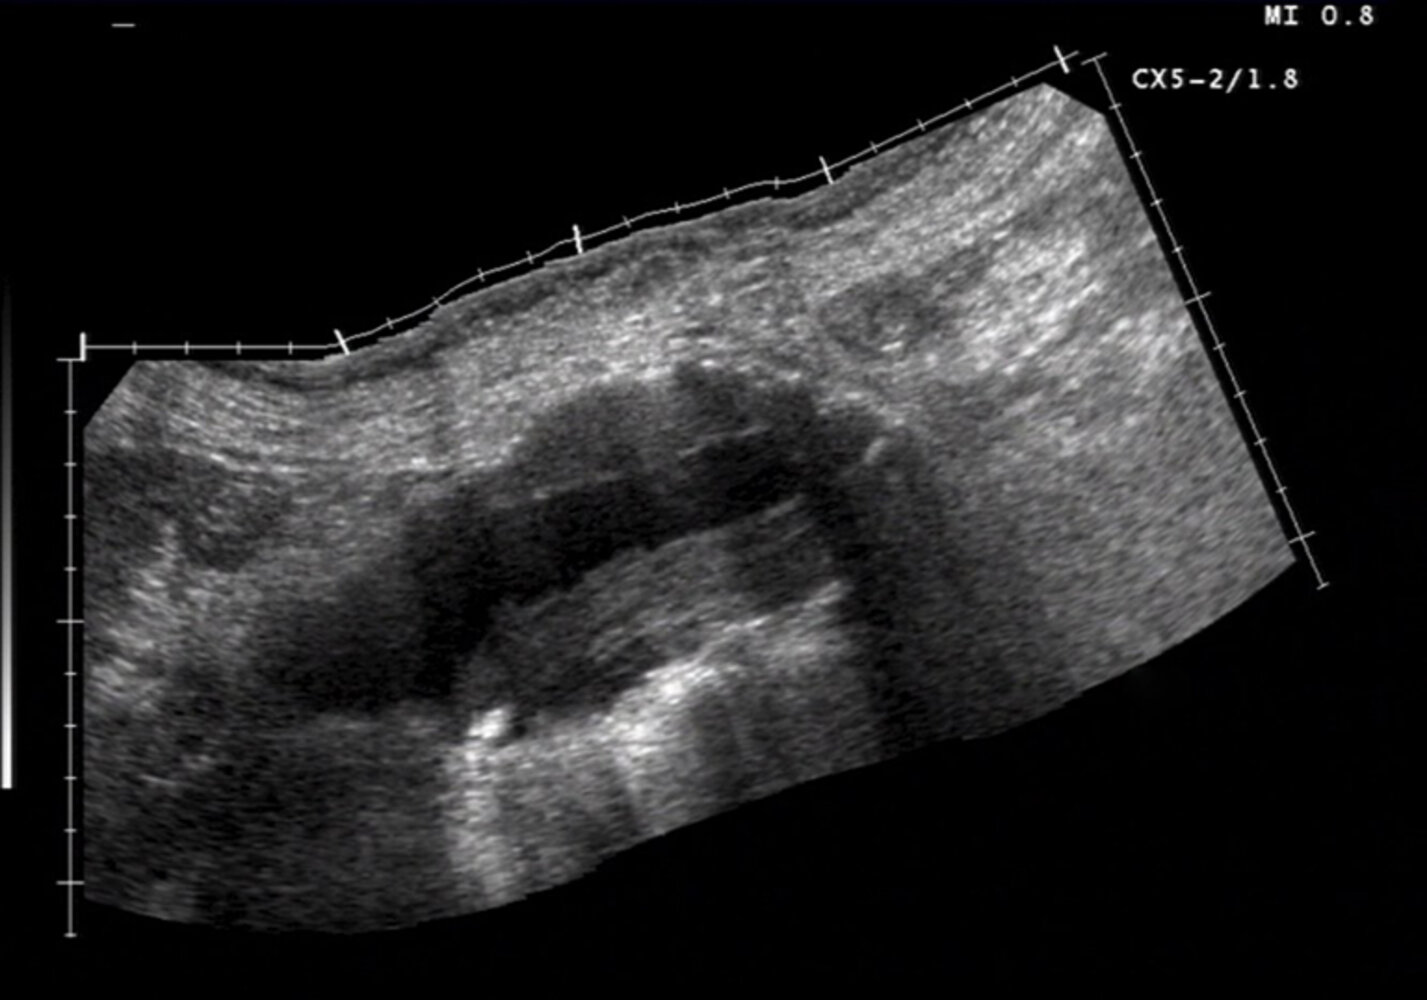

Abdominal ultrasound (formal ultrasound or POCUS)

Best initial and confirmatory test in:

- To determine the presence, size, and extent of an aneurysm

Supportive findings

- Dilatation of the aorta ā„ 3 cm [1]

- Thrombus may be present (hyperechoic)

- Disadvantages: Abdominal ultrasound has low sensitivity for aneurysmal leaks, branch artery involvement, and suprarenal involvement, and its findings are insufficient for procedural planning. [1][9]